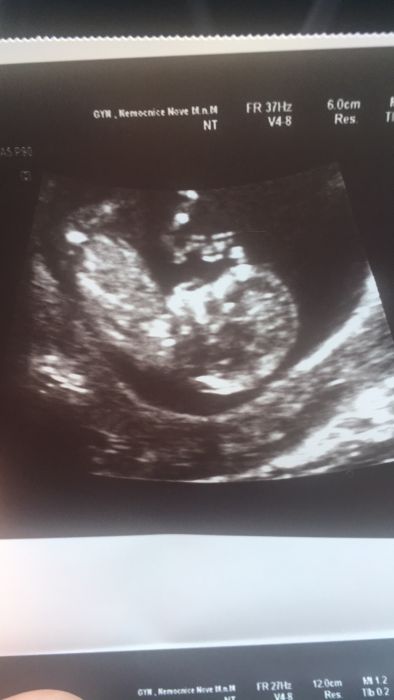

Mam za sebou dnes kontrolu a uz vse v poradku,mimi ma 53,1mm a ma se k svetu,jen je o tyden mensi tak mi posunuly tp na 8.11. pristi uz mam 10.5. prekvapuje me ze porad chce uz. Vubec ho doktor nemohl zmerit,schovava se nejdriv uz prez bricho,pak spodem a nakonec jsem lezela i se zvednutou panvi aby bylo videt???